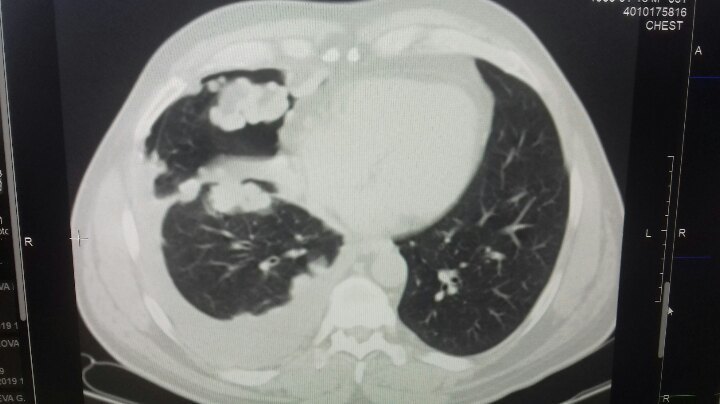

В психологическом плане такое довольно сложно принять. Но!!! Когда все доктора говорят, что у меня онкология, встаёт вопрос о собственной жизни, о её сохранении... ампутация/сохранение ноги было соотношение 9/1. Остеосаркома- вещь хреновая, только резекция , химиотерапия не помогает, только приостанавливает рост раковых клеток и метастаз. Главное- чётко соблюдать рекомендации онколога. Сейчас хожу без палки, метастаз нет( на кт показало) . Врач сказал, что нехер организм травмировать кт. Сейчас раз в 3 месяца только рентген. Хочу отдельно поблагодарить Богдаева Юрия Михайловича и Белякова Сергея Васильевича за то, что спасли мою ногу... хотя 7 марта я был у них один на операции... могли бы ампутировать за час и пойти бухать , но они меня чинили около 10 часов...